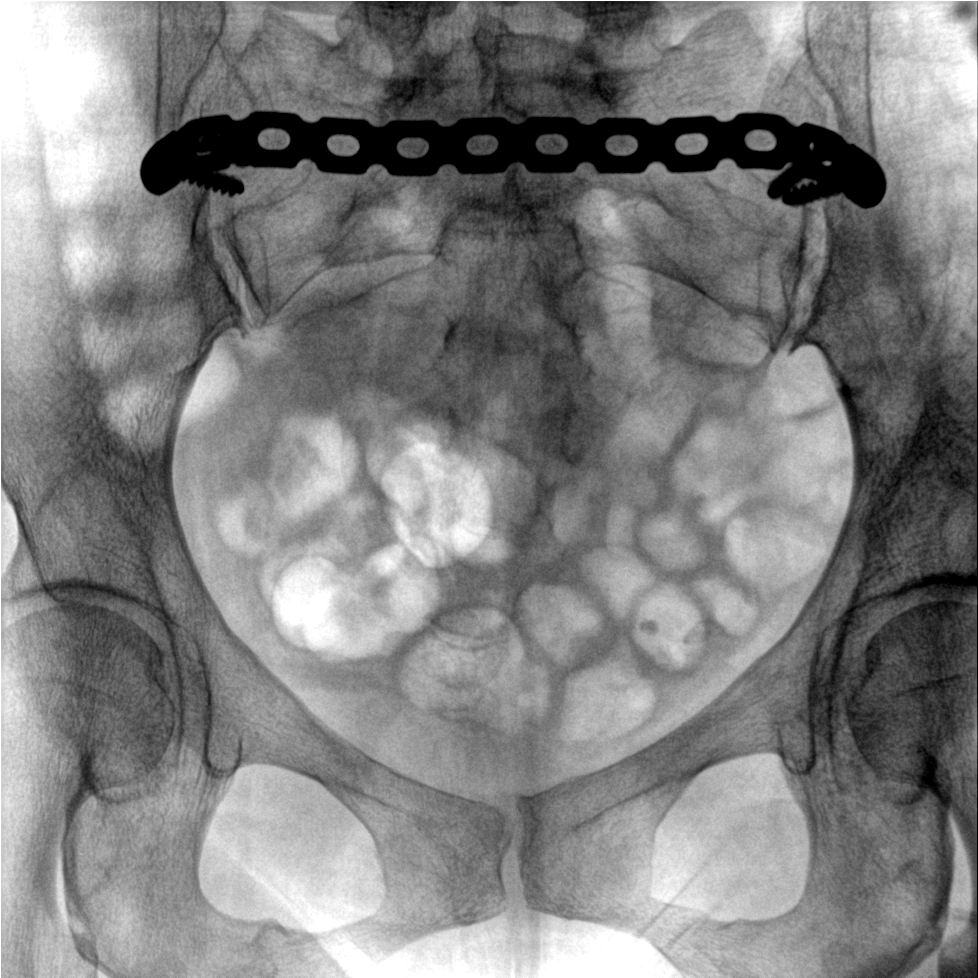

提供更大的術(shù)中三維成像視野,采集更多圖像信息,可一次拍全全段頸椎、全段腰椎、七節(jié)胸椎、雙側(cè)骶髂關(guān)節(jié)、股骨頭及單側(cè)盆骨。